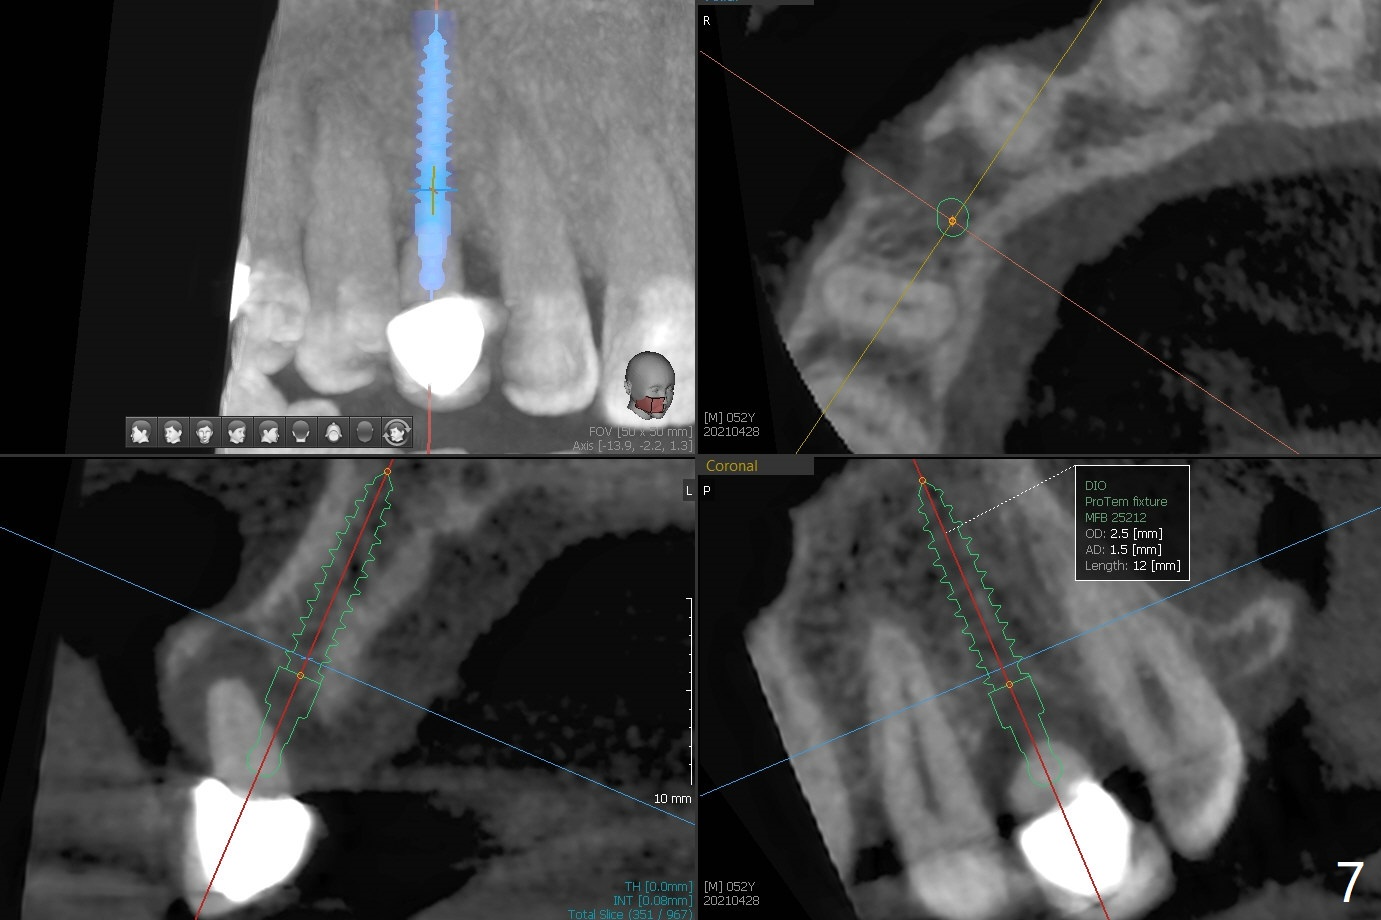

A 52-year-old man requests extraction of the mobile deciduous canine for implant (Fig.1). Use sticky bone (Fig.2 red) to maintain the canine prominence (>). In fact, there is apical perforation of the deciduous canine (Fig.3-5: *). Before bone graft, place a small piece of PRF for repair. The patient refuses to close the diastema between #8 and 9 (Fig.4 ^). Since the cancellous bone is 2.9 mm (Fig.3), it is safe to place a narrow implant (Fig.7). Return to Protect Graft Clindamycin 手术 15 Xin Wei, DDS, PhD, MS 1st edition 04/28/2021, last revision 05/27/2021